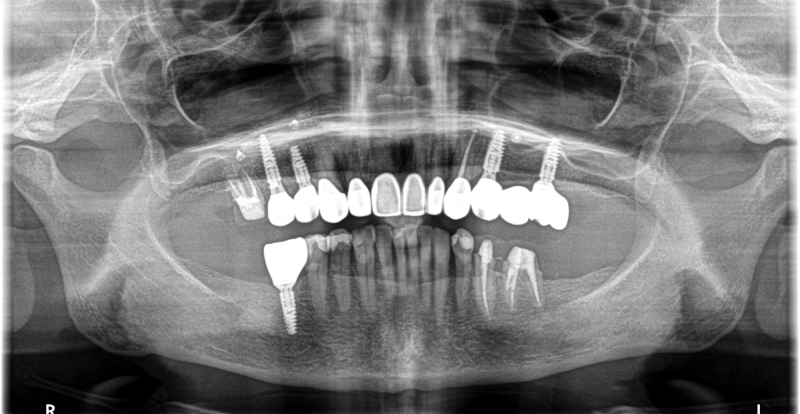

Wykonana praca protetyczna:

- licówki pełnoceramiczne na zębach górnych przednich

- korony pełnoceramiczne na zębach własnych w łuku górnym i dolnym

- korony na implanatch